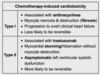

what is the finding

what disease is this finding associated with

thymoma (an anterior mediastinal mass)

-Myasthenia Gravis: will present with dysphagia and unable to swallow = bulbar dysfunction

what is the pathiphysiology of myasthenia gravis

autoAb from the thymus against n-Ach R in the neuromuscular junction –> impaired action potential at receptors –> M wkness

will have weakness that is worse throughout the day, often presents with fatiguable chewing or dysphagia